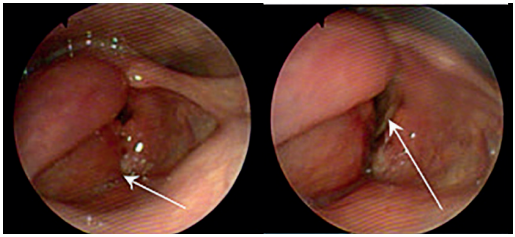

Ante la ausencia de signos duros y la estabilidad hemodinámica de la paciente, con sospecha de lesión aerodigestiva por los hallazgos tomográficos, se inició cubrimiento antibiótico con piperacilina/tazobactam y se decidió continuar manejo expectante. Se realizó un esofagograma que no mostró fugas o lesiones fistulosas (figura 6), y una nasofibrolaringoscopia que documentó un hematoma hemi-laríngeo derecho (figura 7); este examen se repitió a las 24 horas sin observar cambios respecto al estudio inicial. La endoscopia de vías digestivas altas informó la presencia de un hematoma que comprometía la pared lateral de la tráquea, sin embargo, mediante un paso fácil del endoscopio por el cricofaríngeo, no se visualizaron lesiones en el esófago.